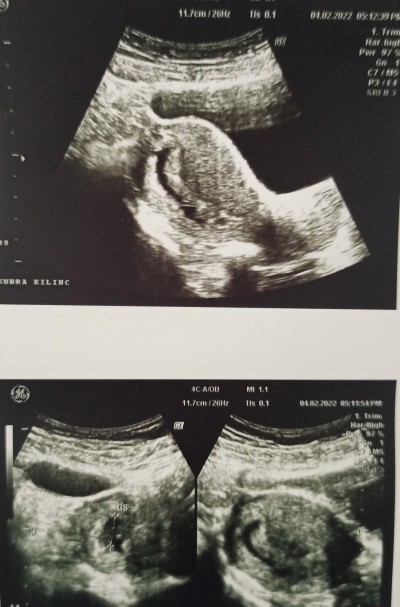

Görselleri değerlendirebilir misiniz ? Embiryo yok.

Reçetede mol gebelik ? Yazmış

He şüpheli belki geç döllenme olmuştur çünkü bende foto çekerken görüntü böyleydi dua et kötü düşünme 2 hafta sonra tekrar git ya da için rahat değilse başka doktora git